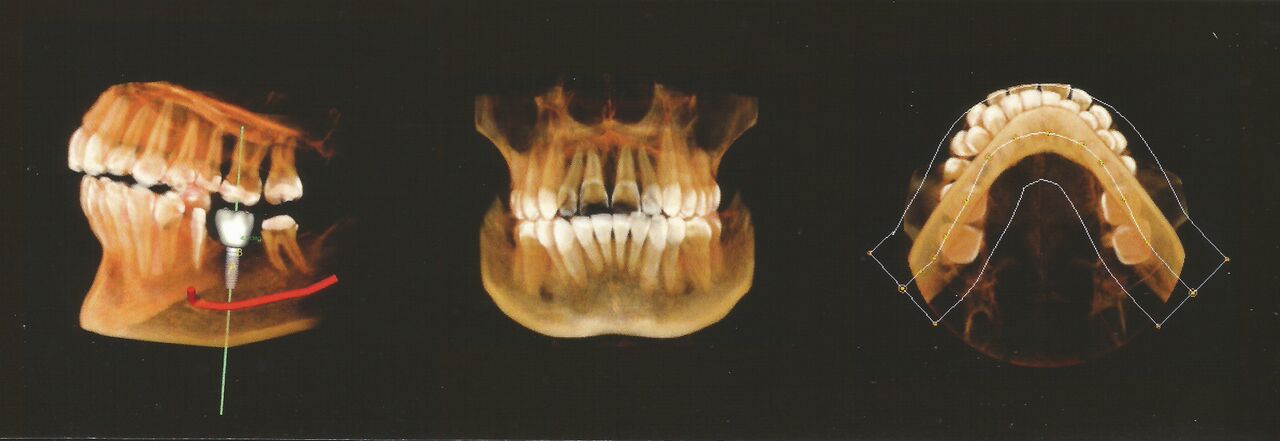

A dental 3D scan allows the clinicians to view the dental anatomy from various angles. A more accurate view of bone structures, such as adjacent root positions, is achieved by 3D scanning in order to locate canals and root fractures, while improving the ability to precisely measure anatomical structures. What makes these scans extremely versatile is the fact that they support a wide range of diagnosis and treatment planning. They also aid in increasing the treatment success rate, providing practitioners more confidence and predictability in preparing for the extractions, conducting root evaluations, and placing implants.

3D dental imaging has proven to be extremely reliable due to its consistency and repeatability providing fast and accurate 3D imagery. The dental professionals may use 3D scanning to get a comprehensive view of specific regions in order to evaluate the situation and to decide whether certain treatment is necessary. The patient too would feel more confident with the dentist's decision on how to carry out treatment as the details are clearly displayed. Furthermore, the patient's dental visit is made more comfortable and engaging by the use of the dental imaging technology.